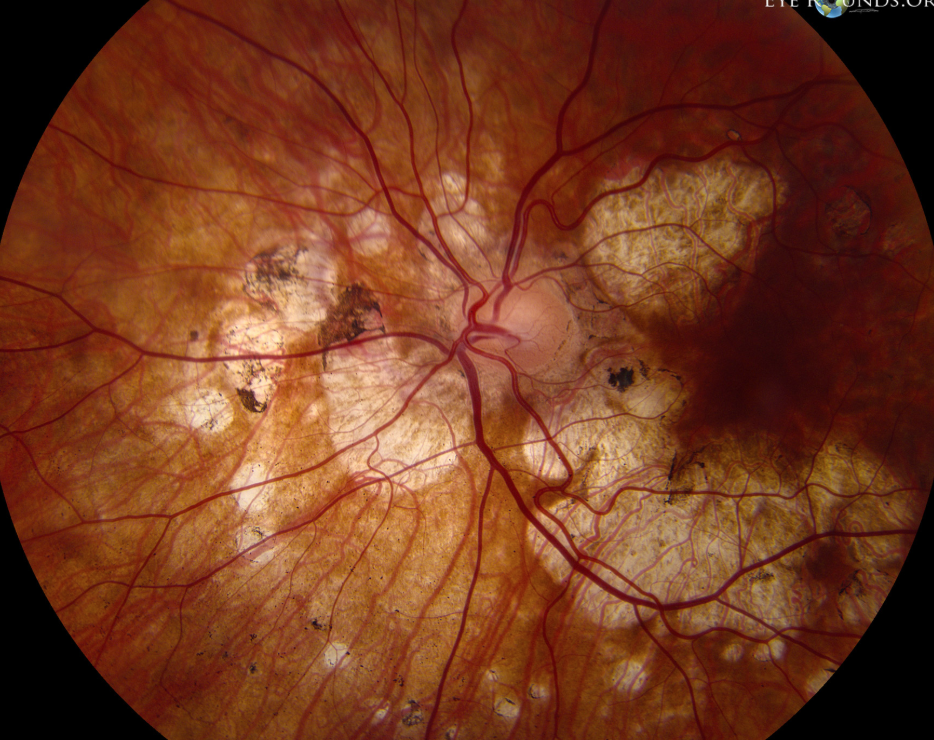

Pathological Myopia/Myopic Degeneration signs?

Tilted disc

PPA (RPE pulls away from the nerve)

Lacquer cracks

Mechanical breaks in Bruch's Membrane

Look like yellow-white "lightning bolts" radiating from nerve

Lacquer Cracks = "Mechanical Stretching" (Fine, irregular, yellow-white "lightning bolt" lines. Usually found in Macula or radiating from Optic Nerve) VS. Angioid Streaks = "Chemical Brittleness" (Thicker, darker, "vessel-like" streaks radiating from Optic Nerve)

CNVM

Fuchs’ spots (dark spots from RPE hyperplasia)

If lacquer crack bleeds → leaves a pigmented scar in macula

Posterior staphyloma (outpouching of post seg as white circles = visible choroid)